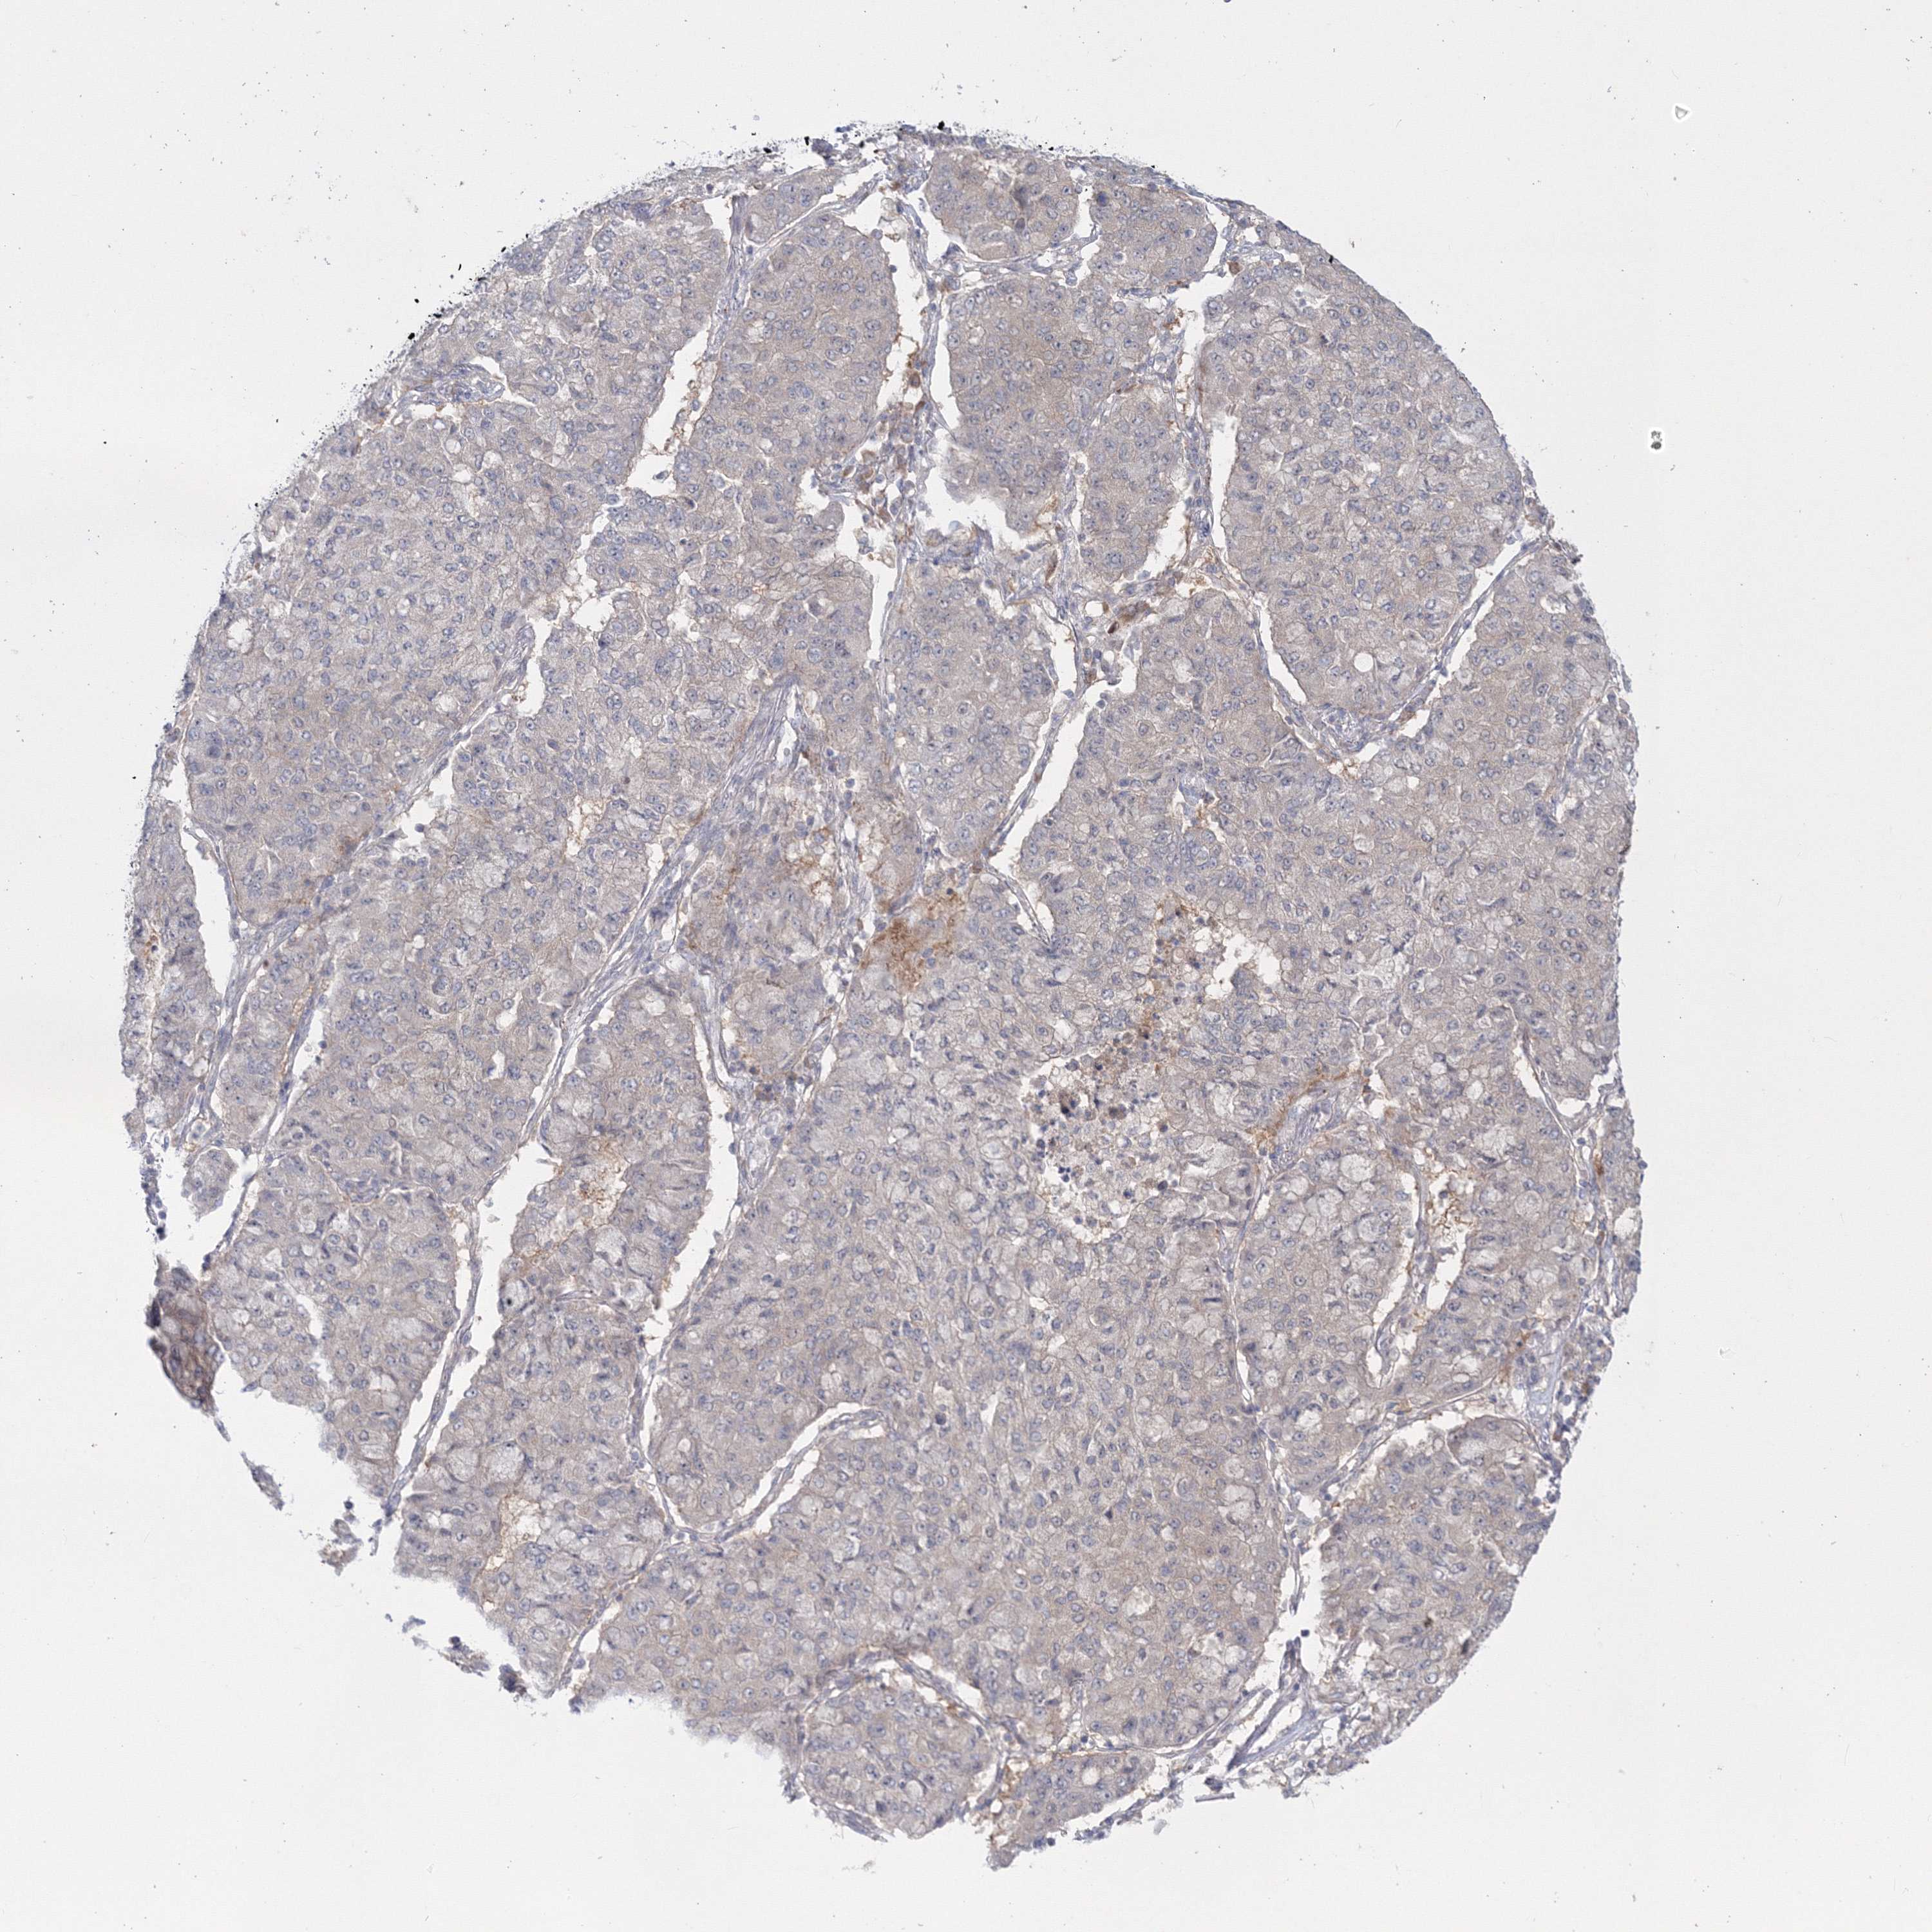

CANCER LUNG CANCER Show tissue menu

Lung cancer

Human cancer

IPMK is not prognostic in Lung Adenocarcinoma (TCGA)

IPMK is not prognostic in Lung Adenocarcinoma (validation)

IPMK is not prognostic in Lung Squamous Cell Carcinoma (TCGA)